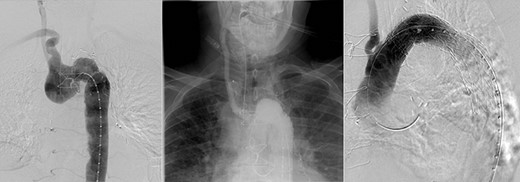

Given the index CTA illustrated a non-dominant right vertebral artery, with known collateralisation of the blood supply to the arm, a decision was made not to perform a carotid subclavian bypass, unless the patient illustrated vertebrobasilar insufficiency. At the second procedure 7 months later, the right subclavian artery was plugged with an Amplatzer (Saint Jude) plug and a GORE (Flagstaff, Arizona) C-TAG stent graft was deployed via femoral access to exclude the Kommerell’s diverticulum and maintain patency of the thoracic aorta (Fig. 3). The post-operative course was uneventful, and the patient was discharged home. There was no immediate noticeable difference in swallowing, however his breathing had improved.

Angiography illustrating Kommerell’s diverticulum before and after deployment of Amplatzer plug (A) to right subclavian and thoracic aortic stent graft (B).